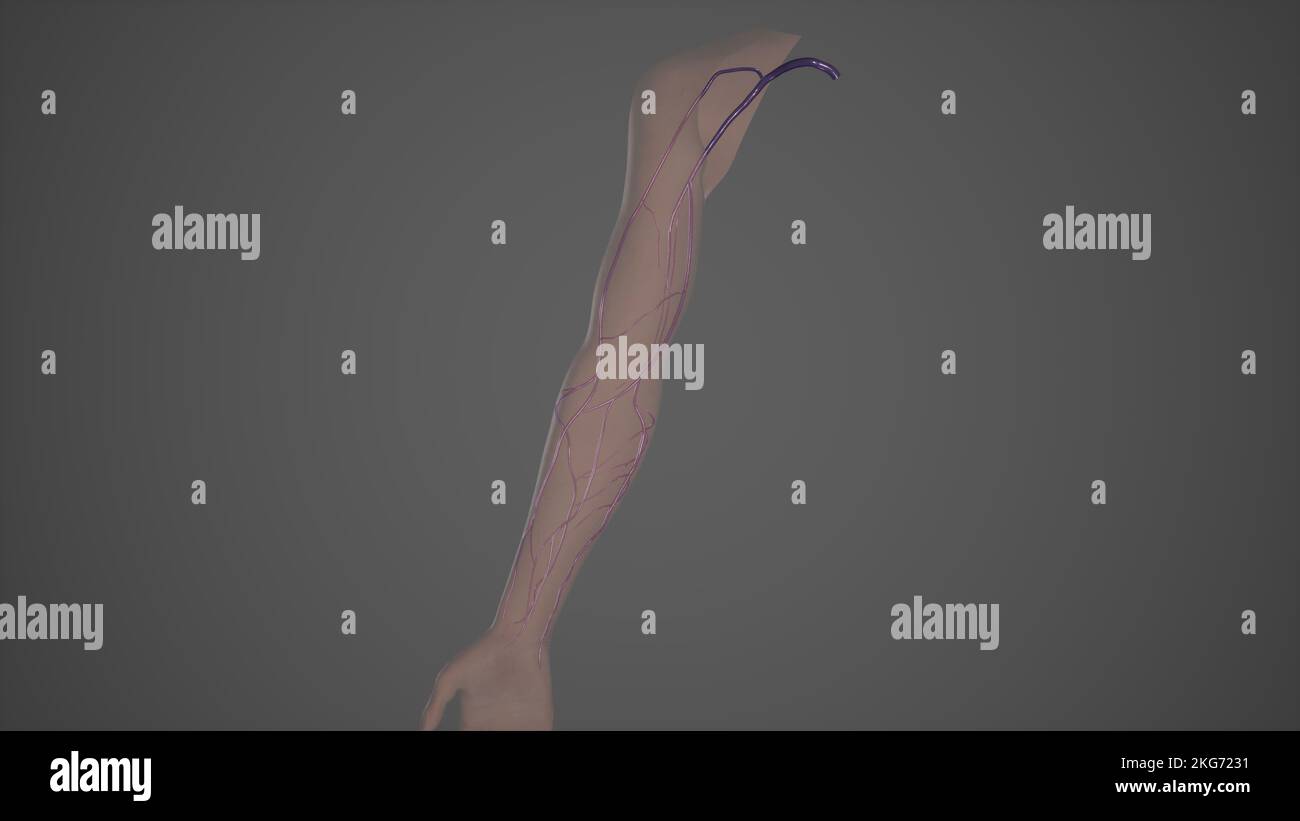

RFEW9HG6–Oberflächlichen Lymphgefäße der oberen Extremität, graviert Vintage Illustration. Üblichen Medizin Wörterbuch - Paul Labarthe - 1885

RFEW91T9–Oberflächlichen Lymphgefäße der oberen Extremität, graviert Vintage Illustration. Üblichen Medizin Wörterbuch - Paul Labarthe - 1885